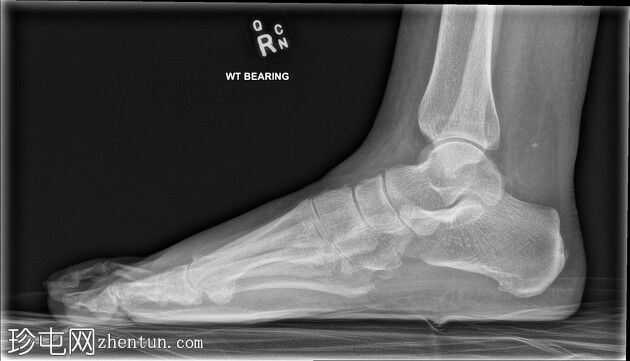

X线片

侧位片

第二趾交叉畸形,跖趾关节伸展,足趾内旋,压在相邻拇趾背侧。

第二趾内旋,压在拇趾上。患者有长期穿高跟鞋的病史。